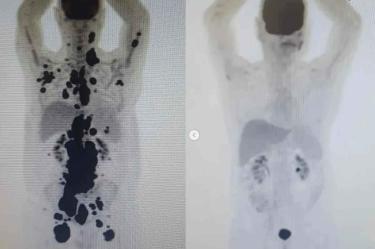

Las imágenes del antes y después de la terapia que Paulo compartió en sus redes sociales y muestran cómo el cáncer desapareció por completo devolviéndole la salud al hombre.

Tras someterse y lograr resultados impresionantes, se difundieron las imágenes del antes y después de la terapia a través de una tomografía computarizada que Paulo compartió en sus redes sociales y muestran cómo el cáncer desapareció por completo devolviéndole la salud al hombre.

“En abril de 2018 estaba en quimioterapia. Era mi segundo cáncer y mi primer linfoma; no tenía idea de que habría dos más por venir. Fueron 1.800 días, decenas de sesiones de quimioterapia y pruebas de imagen, hospitalizaciones, trasplantes de médula ósea, cuatro biopsias, covid, sangrados, UCI... Incluso, los médicos consideraron un milagro que saliera vivo de la hospitalización y la cirugía. Ahora, en 2023, las imágenes del antes y después no dejan lugar a dudas: ¡Remisión completa de mi tercer linfoma! Es el éxito de Cart T Cell”, escribió en sus rede sociales.